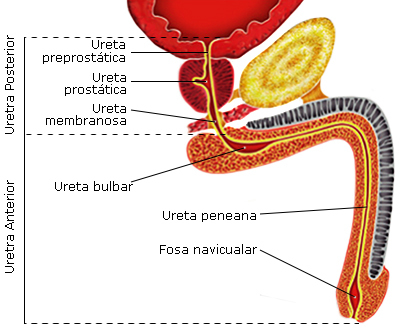

Quando está contraindicada a sondagem vesical para avaliar a reposição volêmica? O que fazer nesses casos?

Sangue no meato uretral, retenção urinária, hematoma perineal, suspeita de fratura de pelve

Antes de sondar, afastar lesão de uretra com uretrocistografia retrograda

,Lesão de qual tipo de uretra…

- Queda a cavaleiro

- Ferimento penetrante, ataque de animais

- Fratura, luxação de bacia

ANTERIOR

Lesão de uretra bulbar: Queda a cavaleiro

Lesão de uretra peniana: Ferimento penetrante, ataque de animais

POSTERIOR

Lesão de uretra memebranosa: Fratura, luxação de bacia